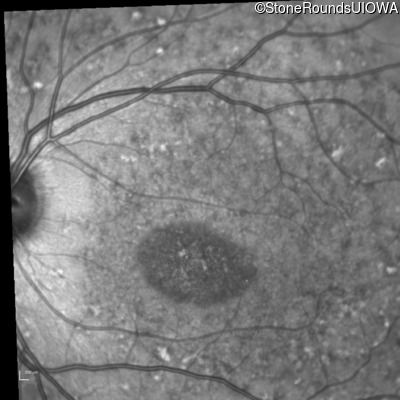

Infrared Fundus Photograph - Right - 20/125 sc

Exemplar